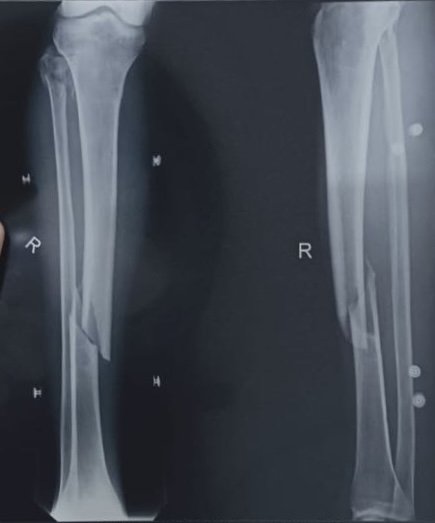

His right leg and left wrist were fractured, and he had some scratches near his right eye. Thankfully, because he was wearing a helmet, he did not have any serious head injuries.

The doctors placed a permanent steel rod in his leg and said it should heal completely. They will have to do a follow-up on his wrist next week to see if it is healing correctly or if he will need another operation.